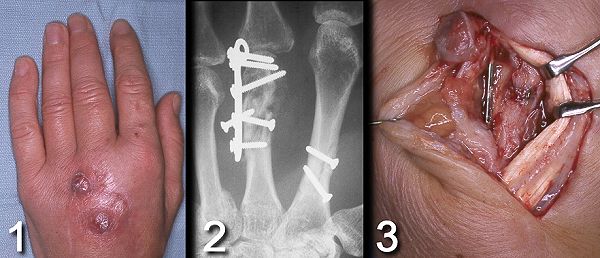

Figure Legend: Osteomyelitis is uncommon

in the hand, usually requiring the combination of severe contamination

and crush injury as in this patient who was kicked by a horse and developed

osteomyelitis after being treated for open metacarpal fractures.